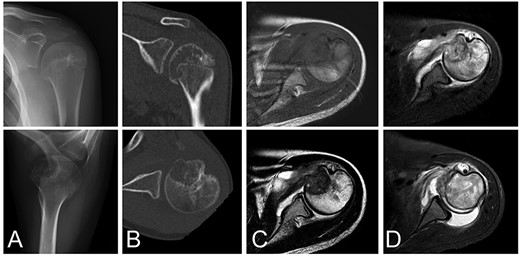

A 13-year-old female who reported left shoulder pain for a year was referred to our institute after she visited a hospital nearby. Her range of shoulder motion was restricted due to pain and tenderness observed over the anterior shoulder. Plain radiographs showed an osteolytic lesion at the anterior humeral epiphysis extending into the subchondral bone (Fig. 1A). Computed tomography (CT) was used to detect an osteolytic lesion with clear margins, and the absence of subchondral bone was indicative of tumoral extension. Calcification within the lesion was observed on the CT image (Fig. 1B). Magnetic resonance imaging (MRI) of the lesion revealed homogenous low signal intensity on T1-weighted images and heterogeneous low signal intensity with partial high foci on T2-weighted images. Bone marrow edema with high signal intensity on T2-weighted images was observed around the lesion. Fluid collection was also evident at the shoulder joint (Fig. 1C–D). Under general anesthesia, an open biopsy was performed, and the diagnosis of chondroblastoma was confirmed. Histological features included a proliferation of round or polygonal cells with well-defined cytoplasm, an eccentric nucleus, and scattered osteoclast-like giant cells.

Chondroblastoma in left humerus of a 13-year-old female. Plain radiographs (A) and commuted tomography (CT) scans (B) show osteolysis with marginal sclerosis in the humeral epiphysis. Calcification is visible in CT images (B). The lesion has homogenous low signal intensity on the T1-weighted image (C-top) and heterogeneous signal intensity on the T2-weighted image (C-bottom) using magnetic resonance images.